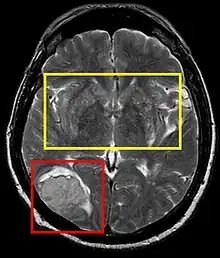

![]() | |

| Stroke brain (similar to cerebral softening) | |

Cerebral softening, also known as encephalomalacia, is a localized softening of the substance of the brain, due to bleeding or inflammation. Three varieties, distinguished by their color and representing different stages of the disease progress, are known respectively as red, yellow, and white softening.[1][2]